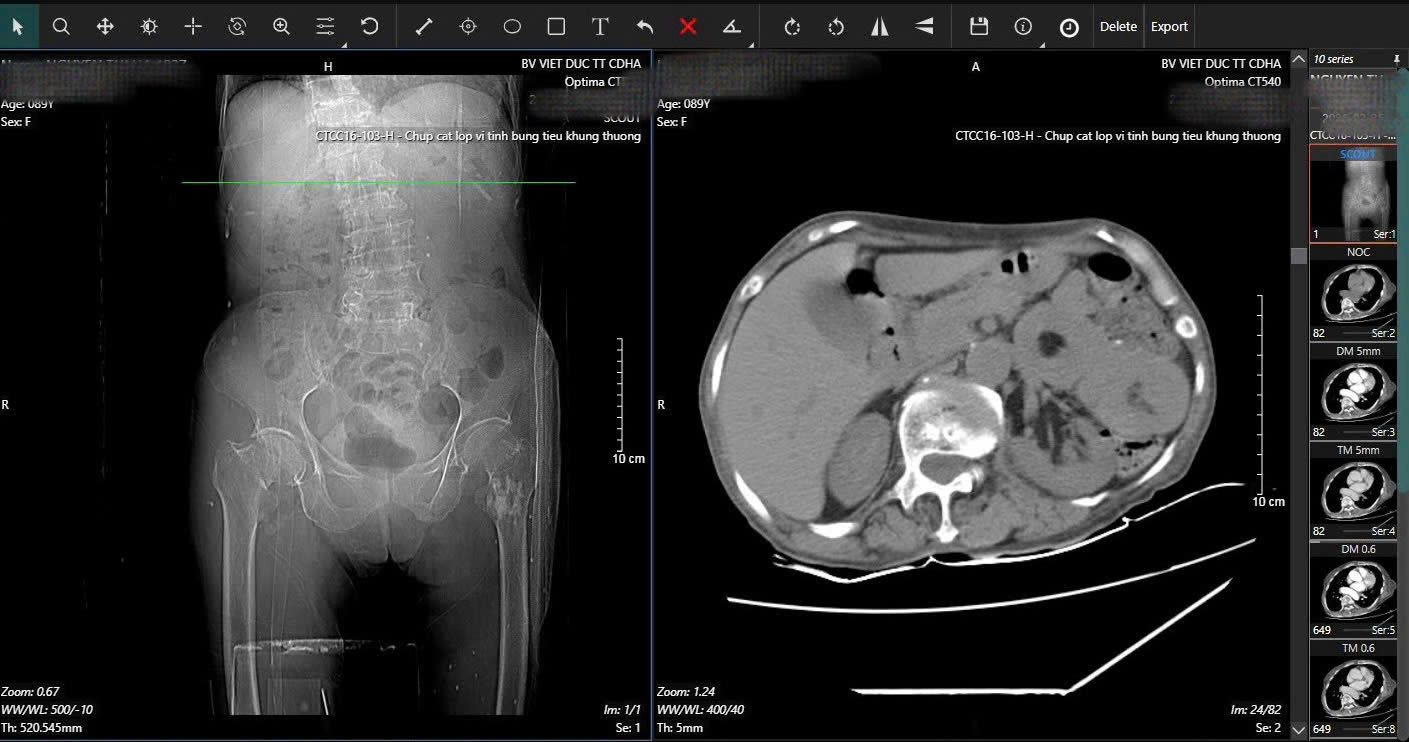

Hình ảnh phim X-quang cụ bà 89 tuổi nhập viện gãy cổ xương đùi phải và hình ảnh chụp CT ổ bụng và phát hiện khối u ruột non gây lồng ruột.

Trong quá trình kiểm tra tổng quát, các bác sĩ BV Hữu nghị Việt Đức phát hiện dấu hiệu bất thường ở vùng bụng. Kết quả chụp CT cho thấy cụ bị lồng ruột do u với khối lồng dài 165mm. Đây là tình trạng cấp cứu nguy hiểm, có thể gây tắc ruột và đe dọa tính mạng nếu không xử lý kịp thời.